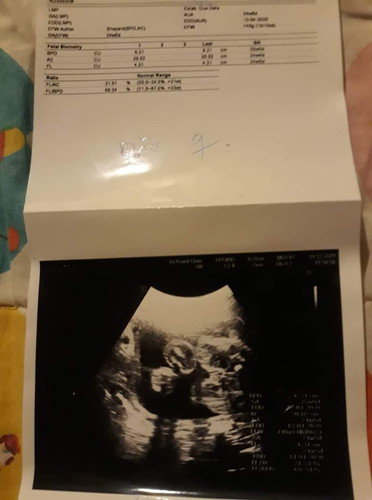

แม่ๆคะ..แบบนี้ได้ผู้หญิงหรือชายคะ..หมอไม่ได้บอกอะไรอ่ะค่ะ..เราก็ไม่ได้ถามด้วยให้แต่ใบนี้มา

เหมือนจะได้ลูกสาวค่ะแม่

ในนี้ไม่มีระบุนะคะ